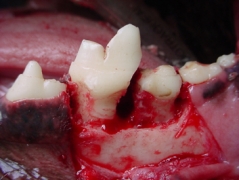

La cirugía en cavidad oral es una de las áreas más socorridas en odontología veterinaria. La extracción dental es el procedimiento que más se utiliza en México sobre todo en perros. La enfermedad periodontal es la causa más común de indicación para la extracción dental, siguiéndole las fracturas dentales por traumatismo y los problemas pulpares. La forma y disposición de las raíces en perros, gatos y otras especies carnívoras, hacen de la extracción un área muy difícil en casos de no existir enfermedad periodontal. En perros los problemas más comunes de extracción dental es de que las raíces de los dientes bi radiculares y tri radiculares están divergentes, por lo que siempre se tienen que seccionar quirúrgicamente las coronas hacia la furcación con el fin de separar las raíces para su extracción como si fueran dientes de una sola raíz aundo con el levantamiento de un colgajo mucoperióstico y ostectomía en la zona vestíbulo cervical. Los caninos es otro problema ya que el tercio medio de la raíz es más ancho que el tercio cervical, por lo que para su extracción se realiza la ostectomía de la cortical externa previo levantamiento de un colgajo mucoperióstico. La extracción de dientes en gatos presenta un problema básicamente y es que sus raíces son muy pequeñas y delgadas por lo que si no se tiene cuidado y paciencia regularmente se fracturan. La mayoría de casos que atendemos en nuestra práctica en gatos es la de restos radiculares por fracturas dentales iatrogénicas.

Haz CLICK sobre la imagen para ver descripción.Extracción del primer molar superior

Extracción de restos radiculares en un gato